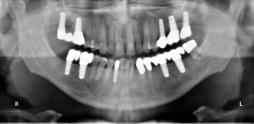

Beispiele für komplexe implantologische Versorgungen aus unserer Gemeinschaftspraxis

(Planung / Endversorgung -- als Röntgenaufnahmen)

C1

C2

C3